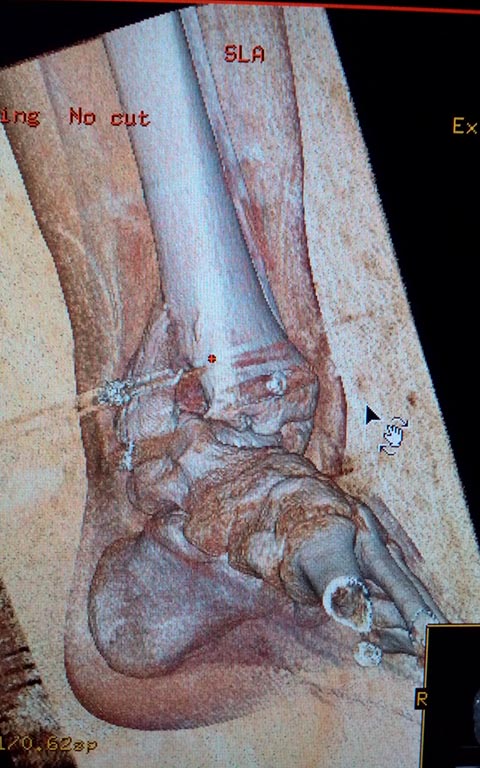

Мужчина, 1987 г.р. получил травму 10.2014. ДТП. Закрытый двухлодыжечный

перелом костей костей левой голени, перелом заднего края большеберцовой

кости с подвывихом стопы кзади, кнаружи. Наложен дистрактор.

Операция 10.2014: закрытая репозиция, остеосинтез спицами,

винтами. В дальнейшем произошло ожидаемое усугубление нарушений

взаимоотношений в голеностопном суставе.

Какой план лечения,на Ваш взгляд, предпочтительнее в данном случае?

Возможно ли одномоментно устранить подвывих или только на аппарате

Иллизарова? Первичные снимки после травмы отсутствуют. Критично ли

"растоптана" латеральная суставная поверхность большеберцовой кости?